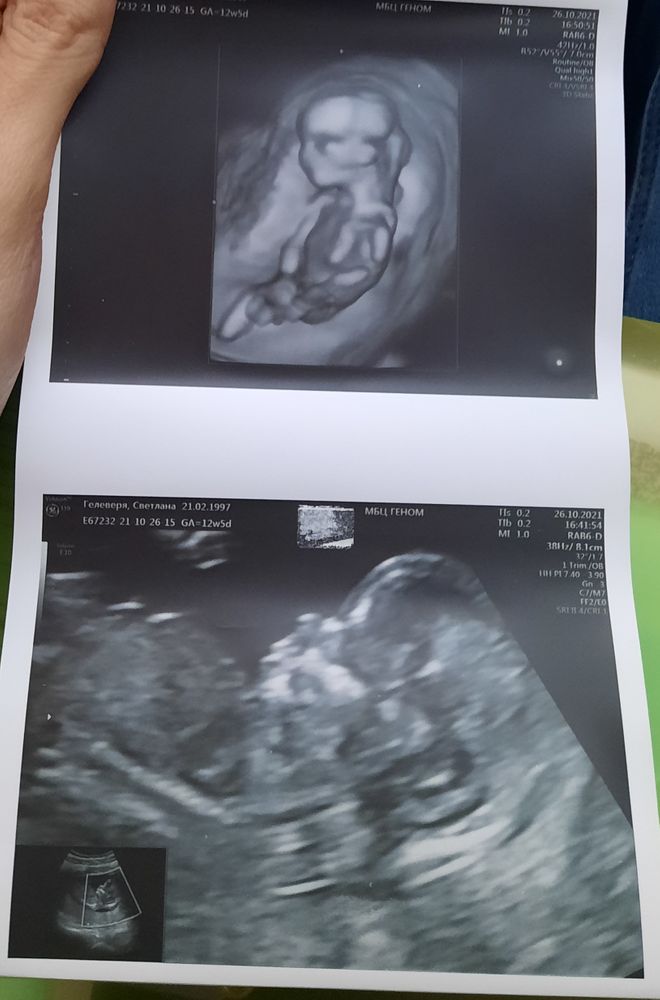

Первый скрининг пройден!

Вот, кстати, да)) видно сына, у меня сын, а сейчас жду дочь и фото с узи абсолютно разные на удивление. Причём именно головешки разные

Мятная мышка, правда? 😅😅 по голове еще не слышала что такие различия) слышала о чсс. У нас сегодня 165, но вроде часто говорят что у мальчиков оно чаще 😁 но вот у нас получилось так. А можно фото вашей принцессы? С первого скрининга) интересно глянуть различия 😁

Класс 😍Малыш просто прелесть) Я уже сама жду нашего первого скрининга, но ждать ещё около месяца)

а мне кажется, очень на девочку похоже! форма черепа

Наталия мечтаю о дочке, ну не знаю, я сколько училась и общалась с медиками - узнавать пол по голове это как на кофейной гуще гадать) мы смотркли все таки где надо) и чсс у нас был 165, тоже теория как у девочки. Но это тоже миф. Но там было видно пипирчик с размер носика, собственно по этому врач и сказал уже.

Поздравляю и мы у Краснова были 22го))))))

Светлана , )))))))))) мне трасвагинально не делал, но на живот нормально так давил, я чтоли упиралась, потом спина болела))))))))))) Тоже с мужем заходили, нам больше в плоскости снимки понравились) Нам тоже врач выдвинул теорию про пол, но подтвердим уже на втором скрининге, к сожалению не у него(

Татьяна, оох, давил знатно. 😅😅 я сходила в туалет конечно прямо перед узд, но потом бежала ещк быстрее 🤣 меня больше болел желудок, точнее кишки тк как раз вздутие сейчас 😒 трансвагинально только глянул пол и яичники. И в 3д отснял буквально раза 3. Но том вообще нифига как для меня не понятно 😅 а кого он вам предположил, если не секрет?) И совпадает ли с вашими внутренними ощвщениями?